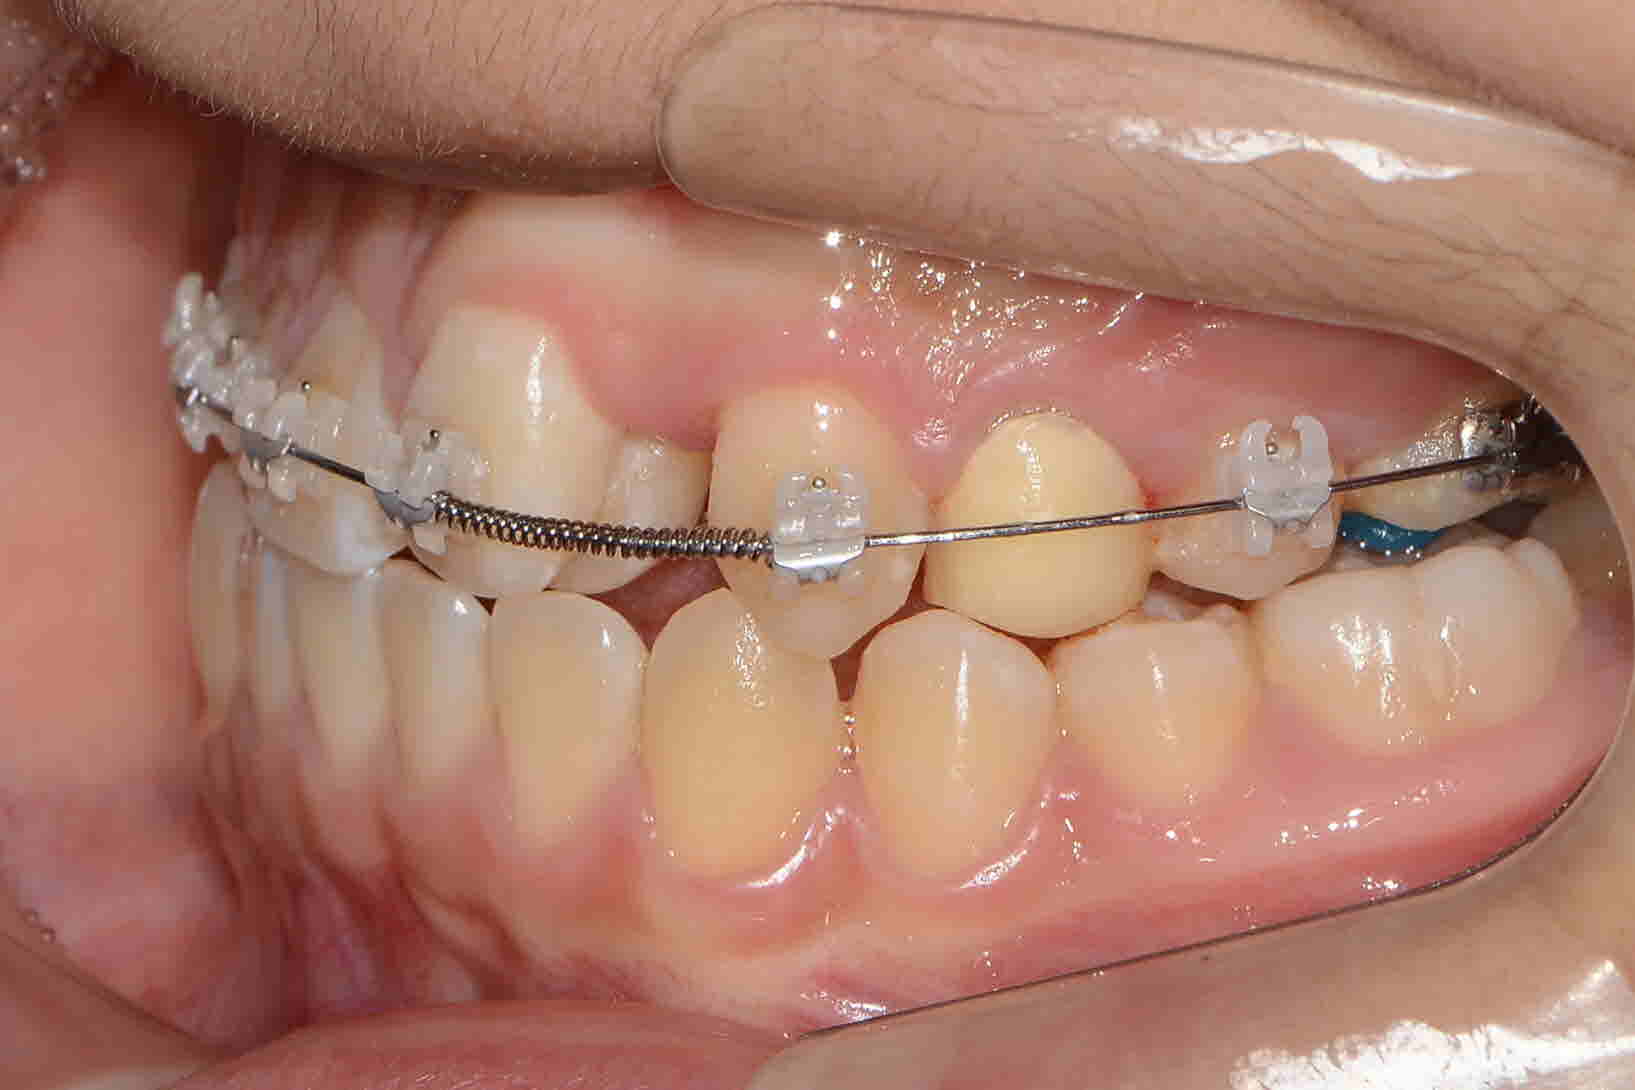

2017년 7월 측면

2018 년 9월 측면

2019년 6월 측면 -